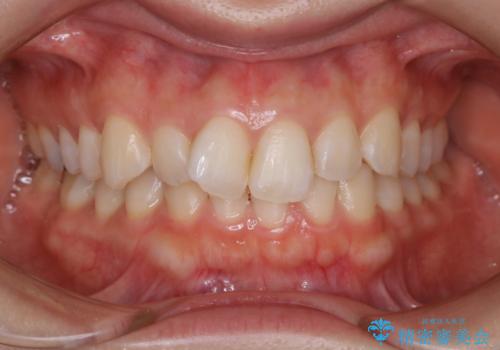

【非抜歯】下の前歯が1本少ない場合の矯正治療

- 前歯のガタつきを主訴に来院されました。

生まれつき下の前歯が1本少なく、その分のスペースを上の前歯がガタつくことで埋めているという状況でした。

上下それぞれのガタつきをとっていく過程で、歯1本分のスペースの差を、上顎の前歯のIPRで調整して並べる方法をご提案させていただきました。